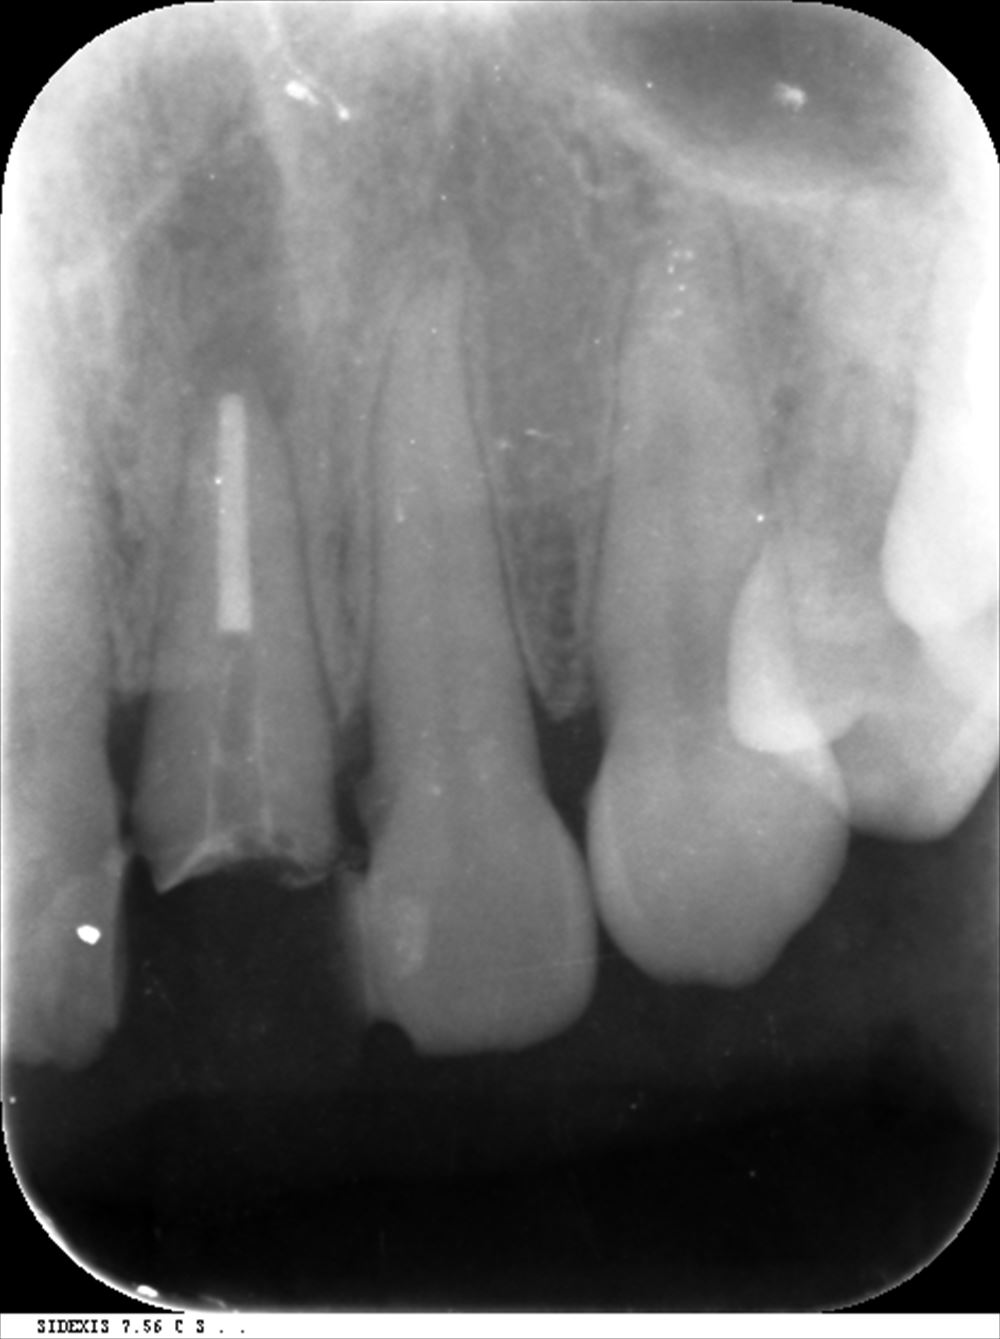

このケースは他院で説明がなく不安で当院に。歯科ドック後根管治療

根の先が見えるようにストレートラインアクセス

根管充填。3回で根管治療終了

術前

術後 症状も消えました!!